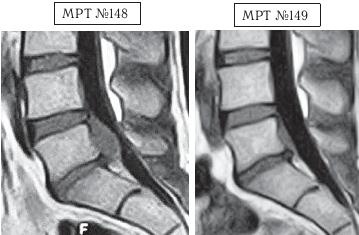

Этот случай особо запомнился своей сложностью, а также большим желанием данного человека восстановить утраченное здоровье.

На МРТ № 148 наблюдается состояние поясничного отдела позвоночника после хирургических операций: рецидив грыжи межпозвонкового диска в сегменте LV-SI, осложнённой массивным секвестром с краниальной миграцией. Размер грыжи до 15 мм дорсально (кзади) и до 34 мм — краниально (вверх).

На МРТ № 149 наблюдается состояние поясничного отдела позвоночника после одного курса лечения методом вертеброревитологии.